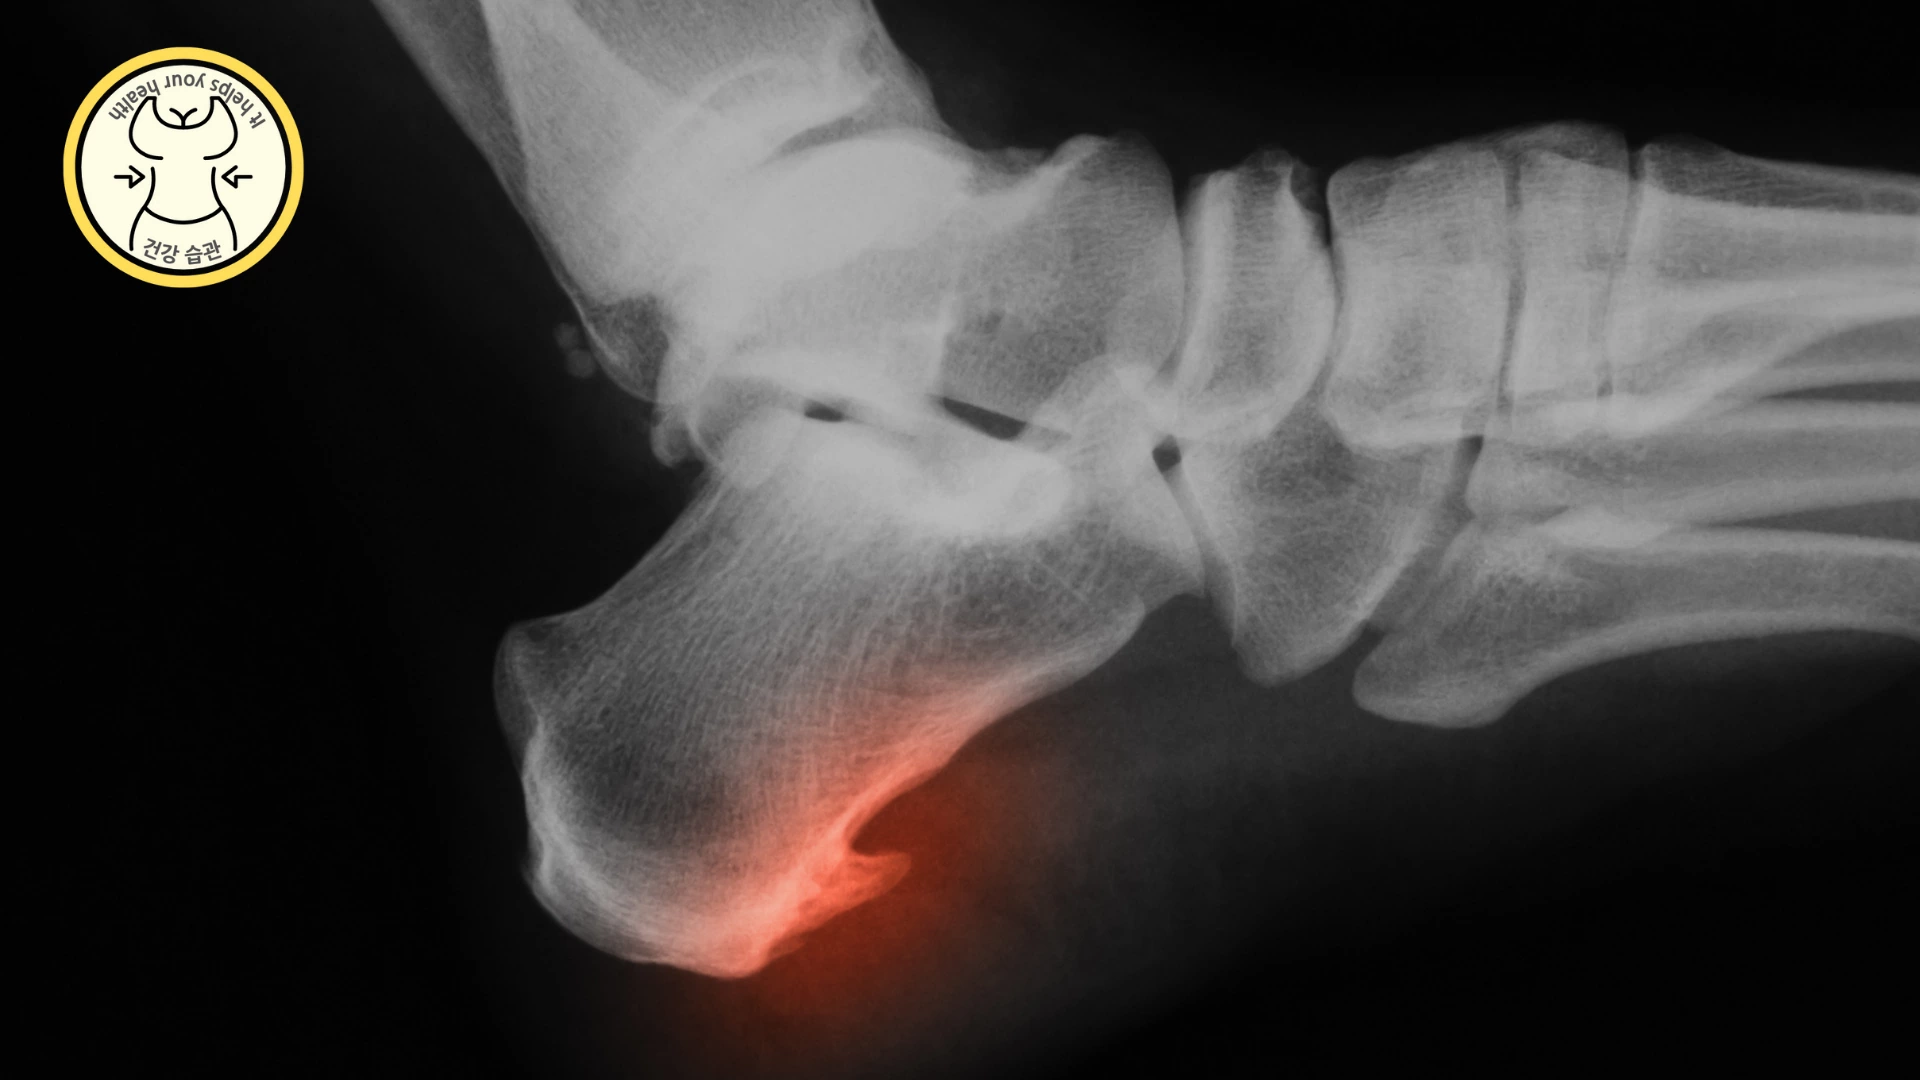

발목터널 증후군

발목터널 증후군이란 해부학적으로는 전방부의 내측 복사뼈, 바깥쪽의 거골 후방 돌기와 재거 돌기, 내측 종아리뼈로 경계를 짓습니다. 발목 터널의 구성을 덮고 있는 부근의 신경들이 외부의 압력을 받아 발생하는 터널 증후군입니다.

발목터널 증후군의 경우 통증이 애매합니다. 주로 저리거나 화끈거리고, 감각이 둔해지는 등 여러 증상이 있는데 걷거나 달릴 때 통증이 또렷해집니다.

이때 신발을 벗고 발을 주무르거나 들면 증상이 사라집니다.